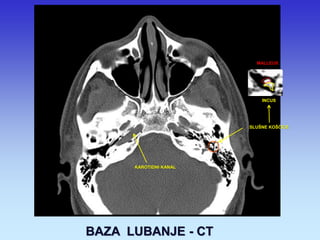

BAZA LUBANJE - CT

KAROTIDNI KANAL

SLUŠNE KOŠĆICE

MALLEUS

INCUS